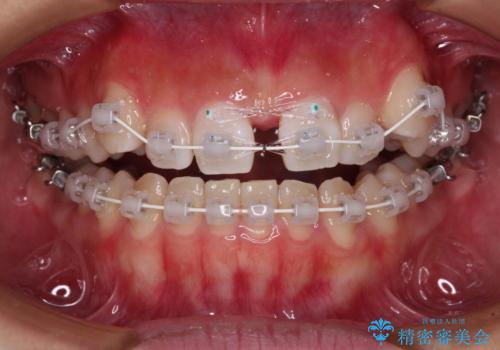

【モニター】上顎が狭い 急速拡大装置を用いたデコボコの解消

- 前歯の開咬と、上顎前歯の八重歯やデコボコを気にして来院された患者様です。

上顎歯列が狭窄していたため、急速拡大装置により上顎骨を側方に拡大し、その後ワイヤー装置にて矯正治療を行うこととしました。

上顎骨を拡大することで、八重歯やデコボコを歯列に収めることができ、下顎の歯が外に位置していた奥歯の咬み合わせも改善することができました。

スペースも短期間に獲得できるため、1年程度で治療を終えることができました。